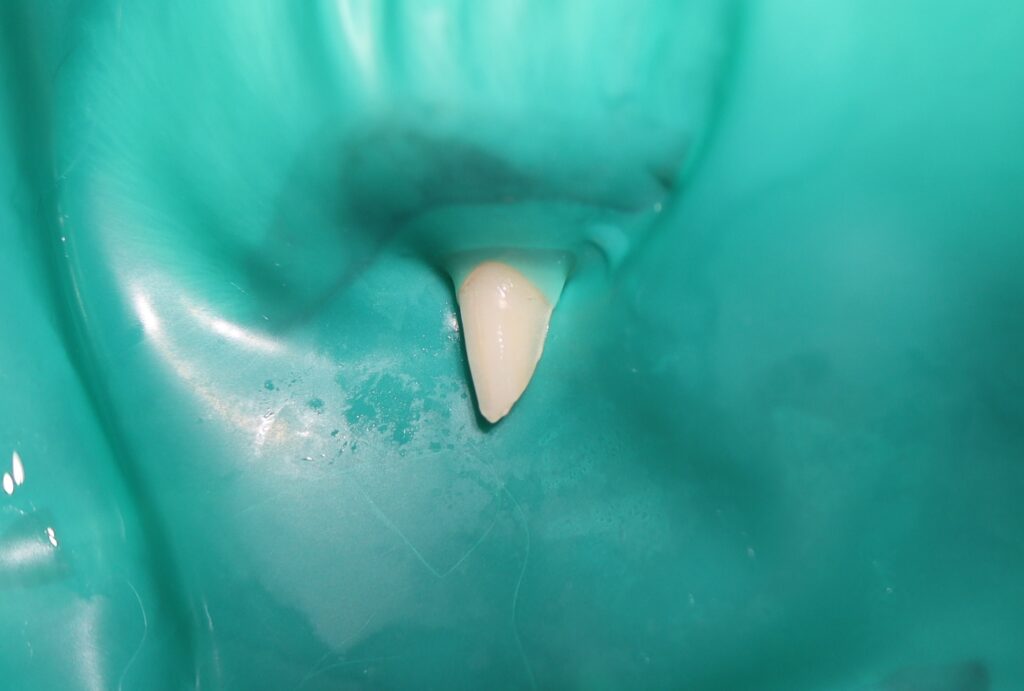

🔧 生活歯髄切断の流れ

- ラバーダムの設置

- 露髄部位の確認と止血

- 病変および象牙質の消毒

- MTAセメントの塗布

- 歯冠修復

この一連の処置により、歯と神経を温存することができました。